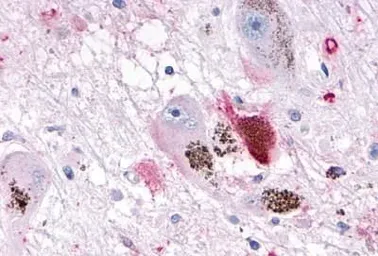

OR10R2 antibody

Cat. No. GTX71527

ApplicationsIHC-P

ReactivityHuman, Rabbit, Bovine, Monkey